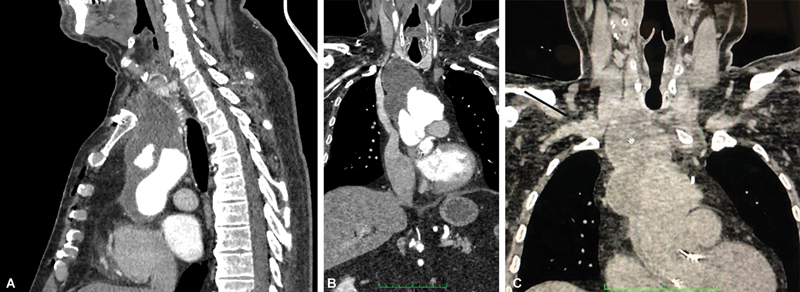

假性动脉瘤的发生会随着原始手术后时间的推移而增加,发生率为 0.2% 至 25%。腋股旁路用于治疗选择性主动脉髂阻塞。腋股动脉旁路术很少反向使用,而且总是用于治疗闭塞性动脉疾病。我们报告了一例吻合口旁主动脉弓假性动脉瘤,并在文献中补充了一种成功的混合治疗方法,即双侧股腋旁路术、所有主动脉上干血栓排除术和主动脉弓内膜覆盖术。

The development of pseudoaneurysms increases with time since the original operation, with incidence 0.2 to 25%. The axillofemoral bypass is employed to treat selective aortoiliac obstructions. Rarely, it is used in reverse form and always for treatment of occlusive arterial disease. We report a para-anastomotic aortic arch pseudoaneurysm and add to the literature a successful hybrid treatment, with bilateral femoroaxillary bypasses, thromboexclusion of all supra-aortic trunks, and aortic arch covering with an endograft.